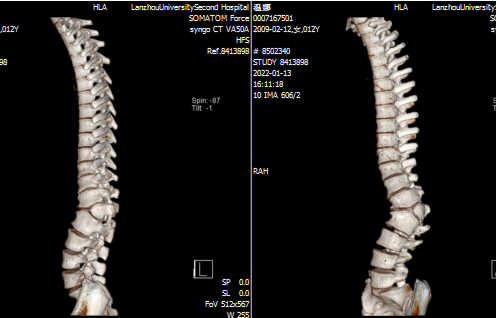

入院后,骨科二病区马延超主任医师诊断该患者胸腰段侧后凸畸形,腰1、腰2椎体形态失常,腰2椎体呈半椎体畸形改变。对于患者的情况,目前国际上公认的治疗方案是通过外科手术,完整切除半椎体,矫正局部畸形,重建脊柱的矢状面与冠状面平衡。

马延超团队结合患者的症状、体查情况、影像学资料,以及脊柱骨盆测量参数,为患者制订出个体化治疗策略和周密的手术方案。在手术置棒矫形过程中,由于局部侧后凸畸形,常规的置棒方式不但置棒困难,而且顶椎区域应力过大易造成矫形棒断裂或者螺钉松动,可能导致矫形丢失,畸形进展,需二次手术翻修。

马延超采用国际上先进的矫形理念,采用半椎体整块切除技术联合多棒序贯矫形技术,短棒负责矫正局部畸形,长棒负责矫正区域畸形和整体平衡,化整为零,分段矫形,不但大大提高了矫形的安全性和有效性,还有效降低了术后并发症,获得满意的临床效果。